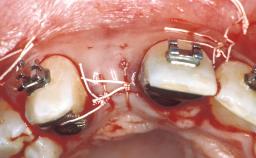

| Jaw | Maxilla and Mandible |

| # of Teeth | 9 |